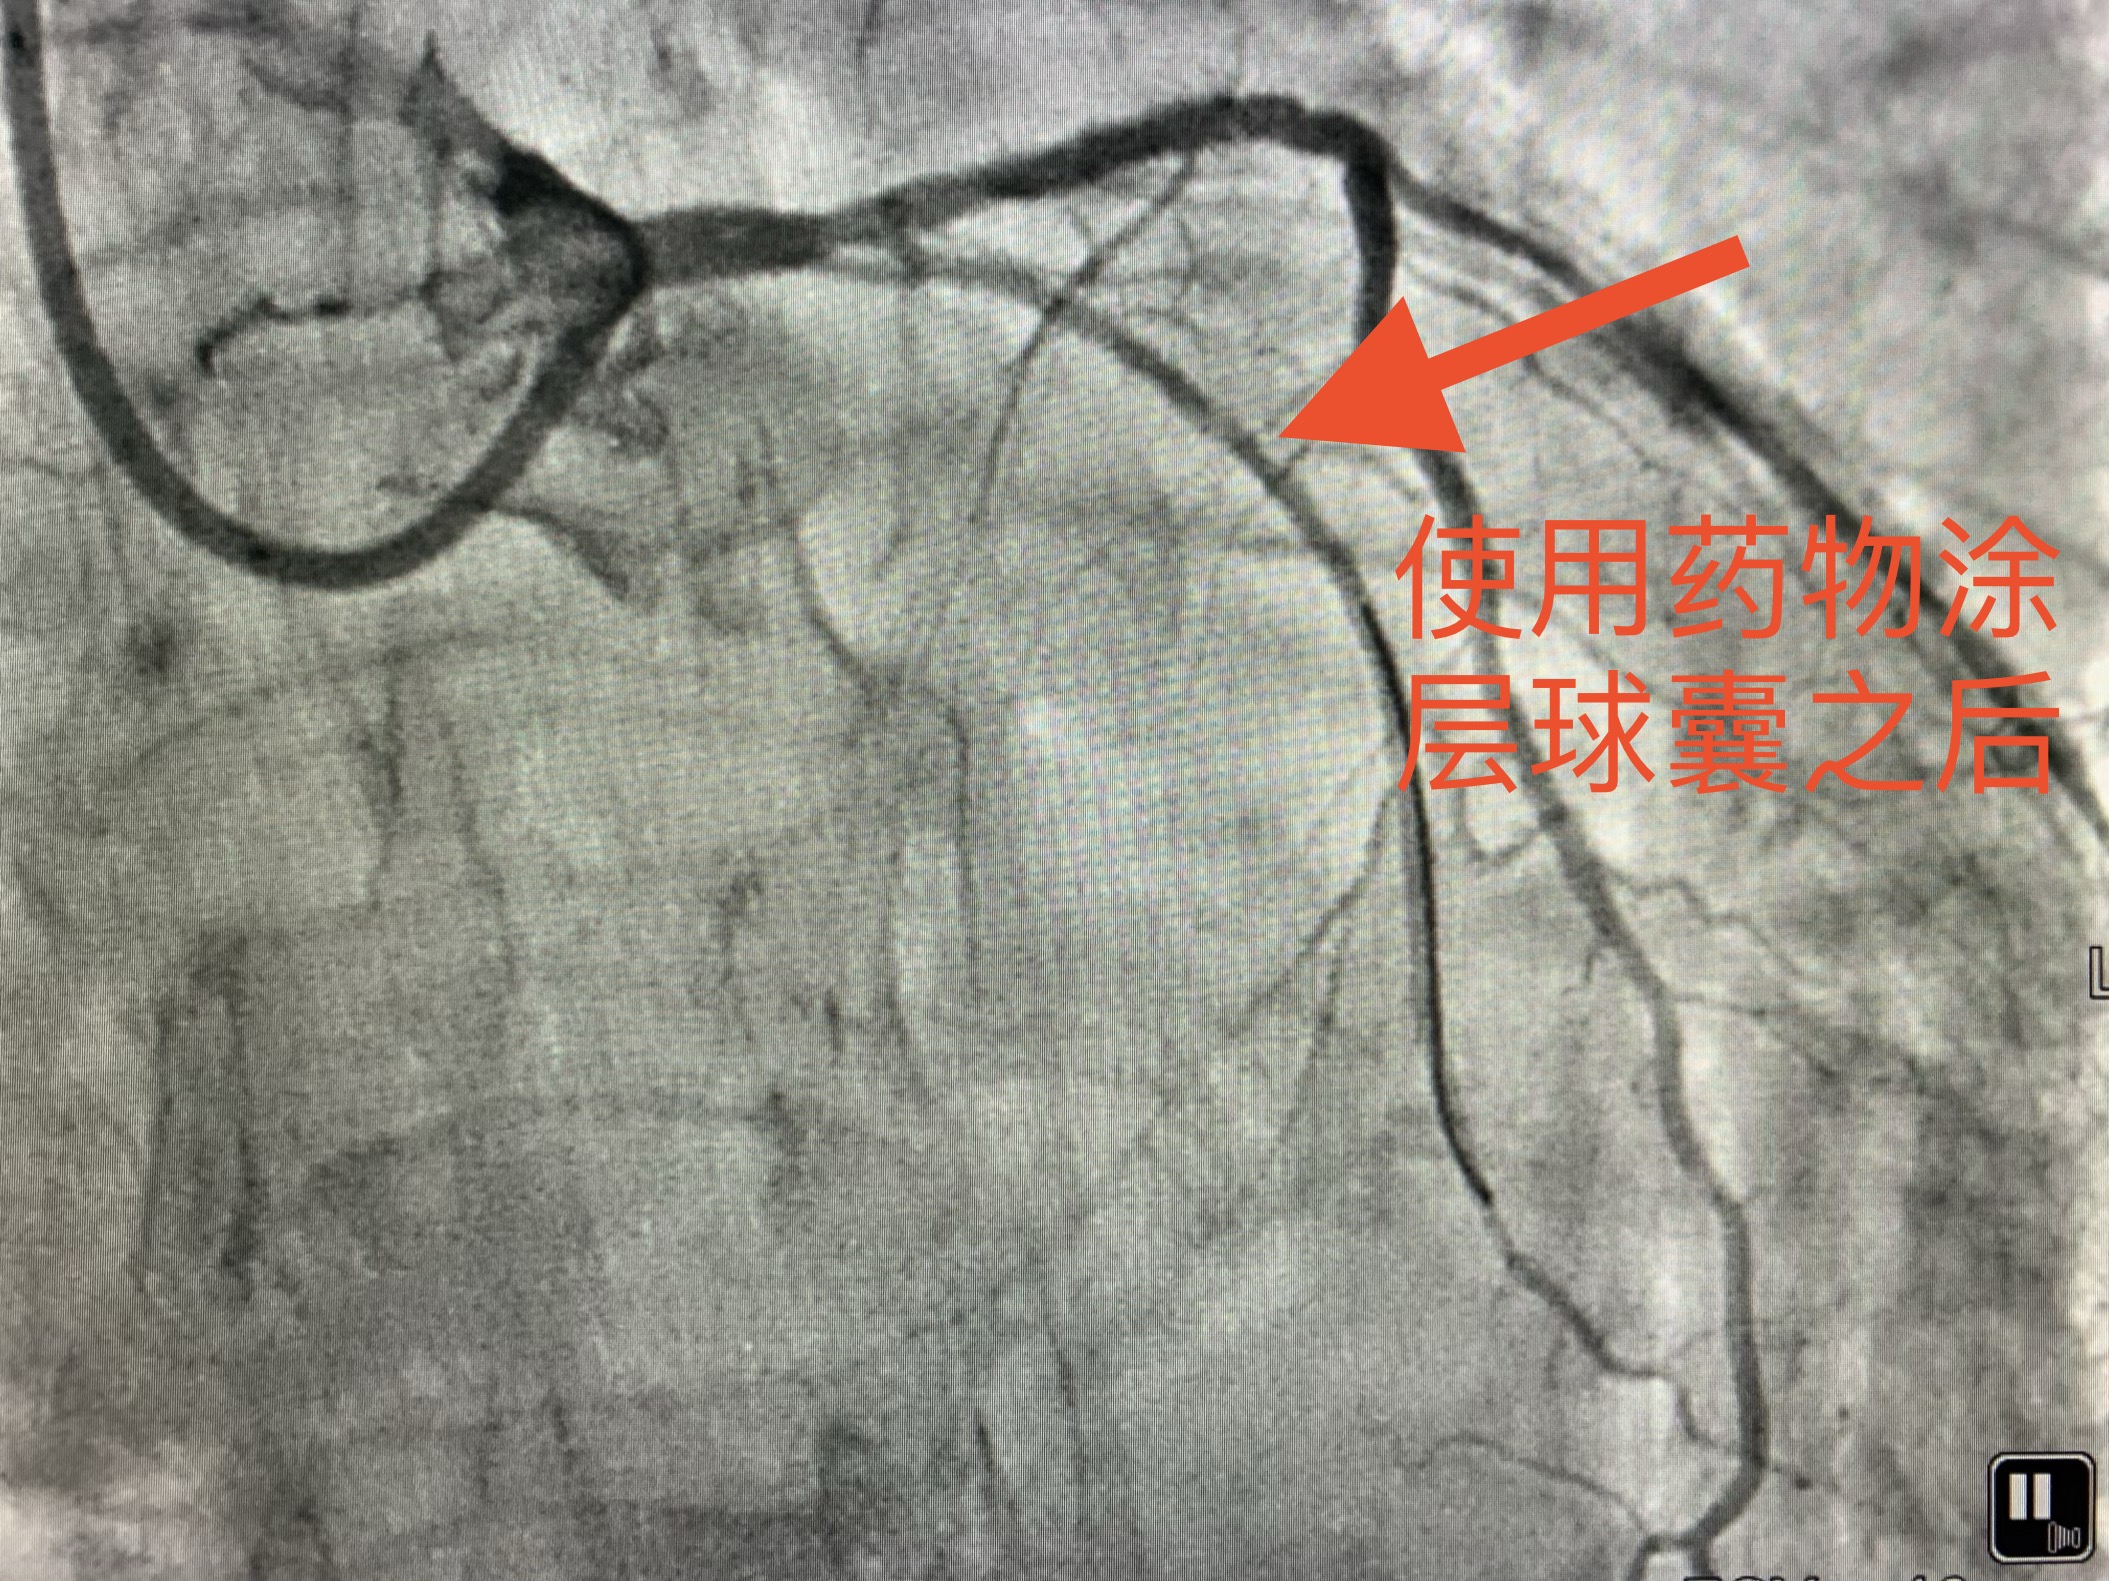

术后老赵身体恢复的很快,再也没有出现胸闷、胸痛的症状。老赵对治疗效果感到非常满意。(使用药物涂层球囊介入处理后的效果见下图)